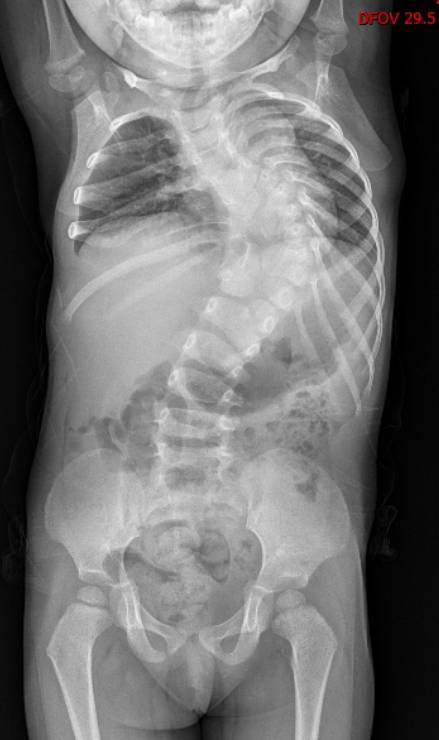

脊椎“大楼”一片废墟

女童可可(化名)家住新洲,先天性椎体发育畸形。自出生起,她的脊柱就向左倾斜,整个身体异常扭曲。随着成长,弯曲日益加重。2岁时,可可脊柱倾斜度数已达到90度——上半身几乎被“折”成了直角。可可四处求医,可都因为畸形严重且复杂,矫形难度大,年龄小且治疗周期长,未来治疗存在不可预测性,迟迟没能得到有效救治。

“如果把脊椎比作一栋大厦,她的第5胸椎到第3腰椎,一共11个脊椎就像11层楼,成了一片废墟:有的‘楼层’合并,有的被拆成两半,有的缺失‘墙体’,没有一处是正常的。”周治国这样形容。

当年,可可年仅2岁半,是生长发育的快速生长期,这样严重的结构畸形,导致胸腔空间的减少,直接压迫了孩子的脏器。手术必须得做,而且需要尽快,这不仅是为了“挺直”脊梁,更是为了“保命”。

9年“生长棒”脊柱矫形撑起生命空间

2015年,2岁半的可可在武汉儿童医院接受了一期手术。专家在可可的胸椎和腰椎上植入了4根生长棒和8枚椎弓根钉当“支架”,尽可能多地给扭曲的脊柱以支撑,延缓脊柱侧弯的进展,同时为胸腔和内脏争取生长空间。

时间一天天过去,可可一点点长大,在医生的控制下,她脊柱侧弯度数从90度降至72度,这也为终末期矫形手术争取到了机会。

截骨手术从72度降至30度

2025年,可可年满12岁,胸腔、胸廓已基本发育成熟。周治国团队决定是时候对最严重的顶椎“动手”了。医生利用3D打印技术,1:1还原了畸形脊柱的脊柱模型,制定了截骨矫形的手术方案。

整场手术足足进行了10个多小时,周治国团队避开脊柱周围的神经和血管,对可可畸形弯曲最严重且最突出的顶椎进行截骨、重整、固定。当手术进入尾声时,可可脊柱的侧弯度数从72度改善至30度,可像正常人一样生活。